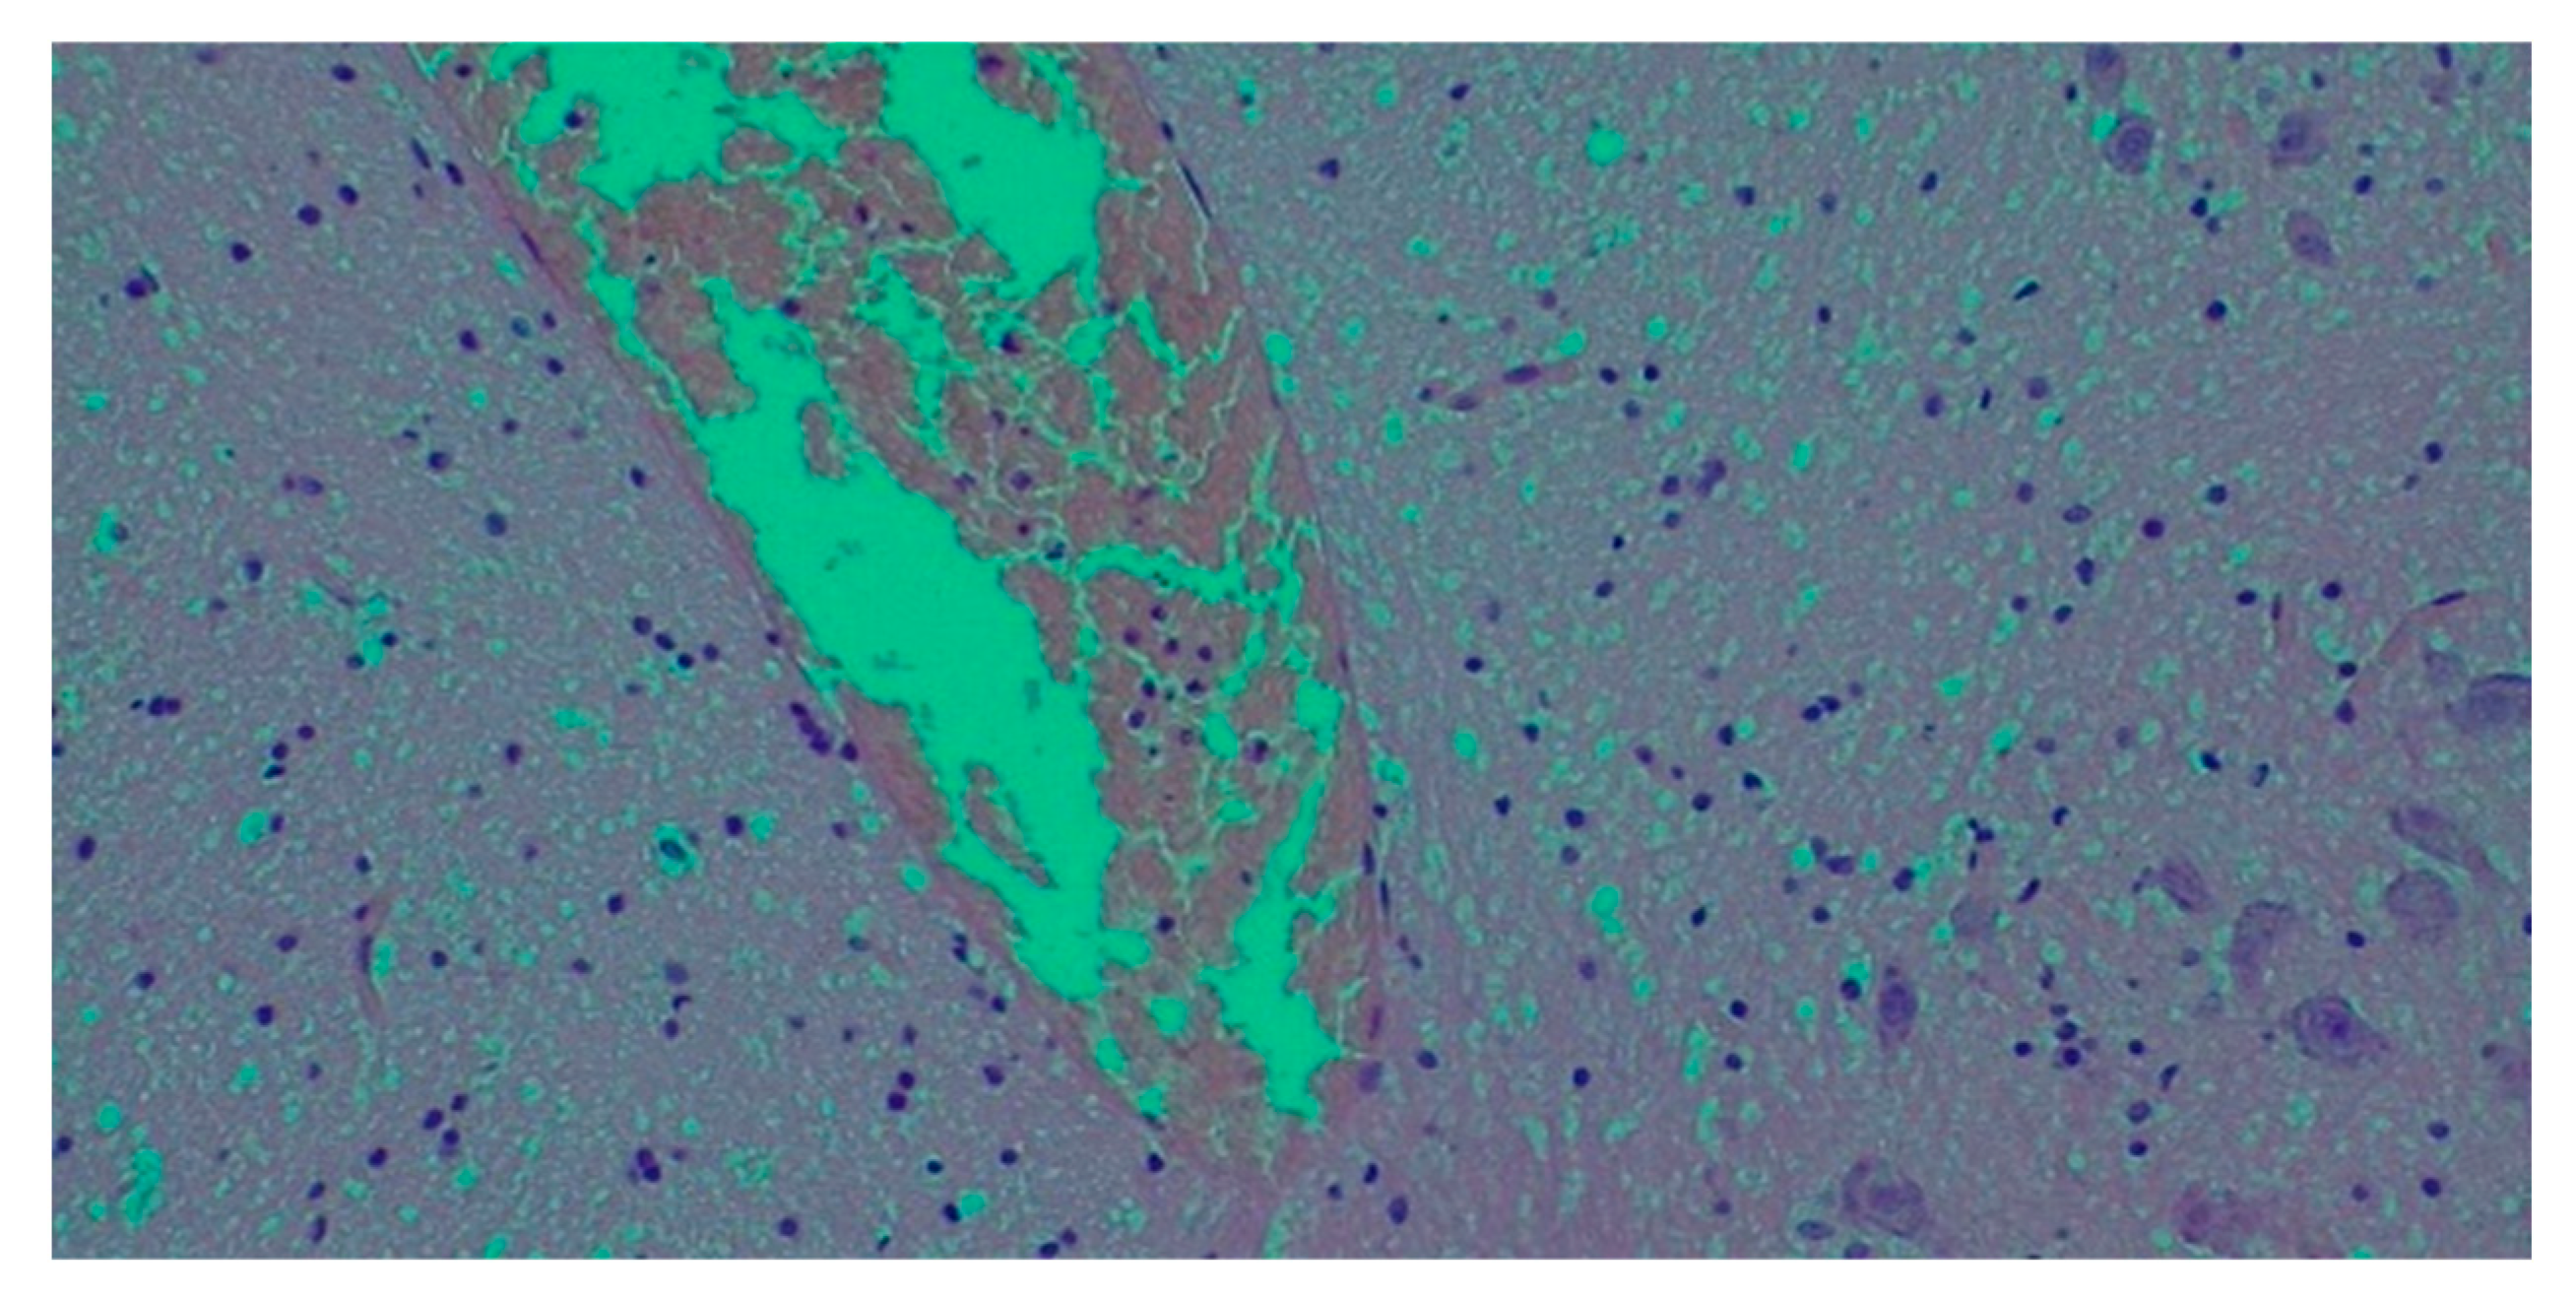

- Histological findings